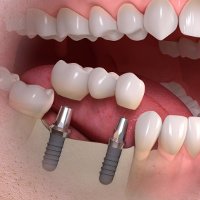

Un impianto è l'alternativa più moderna della sostituzione dentale permanente. Le metodiche di implantologia prevedono principalmente due tecniche chirurgiche:

two stage: in due fasi, la prima "sommersa", ovvero con inserimento dell'impianto, sutura sottomucosa e successiva riapertura della mucosa dopo 2-6 mesi ed avvitamento del"pilastro dentale" sull'impianto;

one stage: inserimento dell'impianto, che viene lasciato transmucoso, emerge la testa dell'impianto, si potrà così o lasciare guarire (sempre per 2-6 mesi) per integrazione ossea o caricare immediatamente, con apposito pilastro dentale, in modo provvisorio o definitivo, a seconda dei casi. Naturalmente gli impianti monoblocco sono obbligatoriamente impianti one stage a carico immediato.

Gli impianti possono sostituire un dente singolo (corona su impianto), un gruppo di denti ravvicinati (ponte su impianti), un'intera arcata dentaria, oppure possono servire a stabilizzare una protesi totale superiore o inferiore (overdenture)